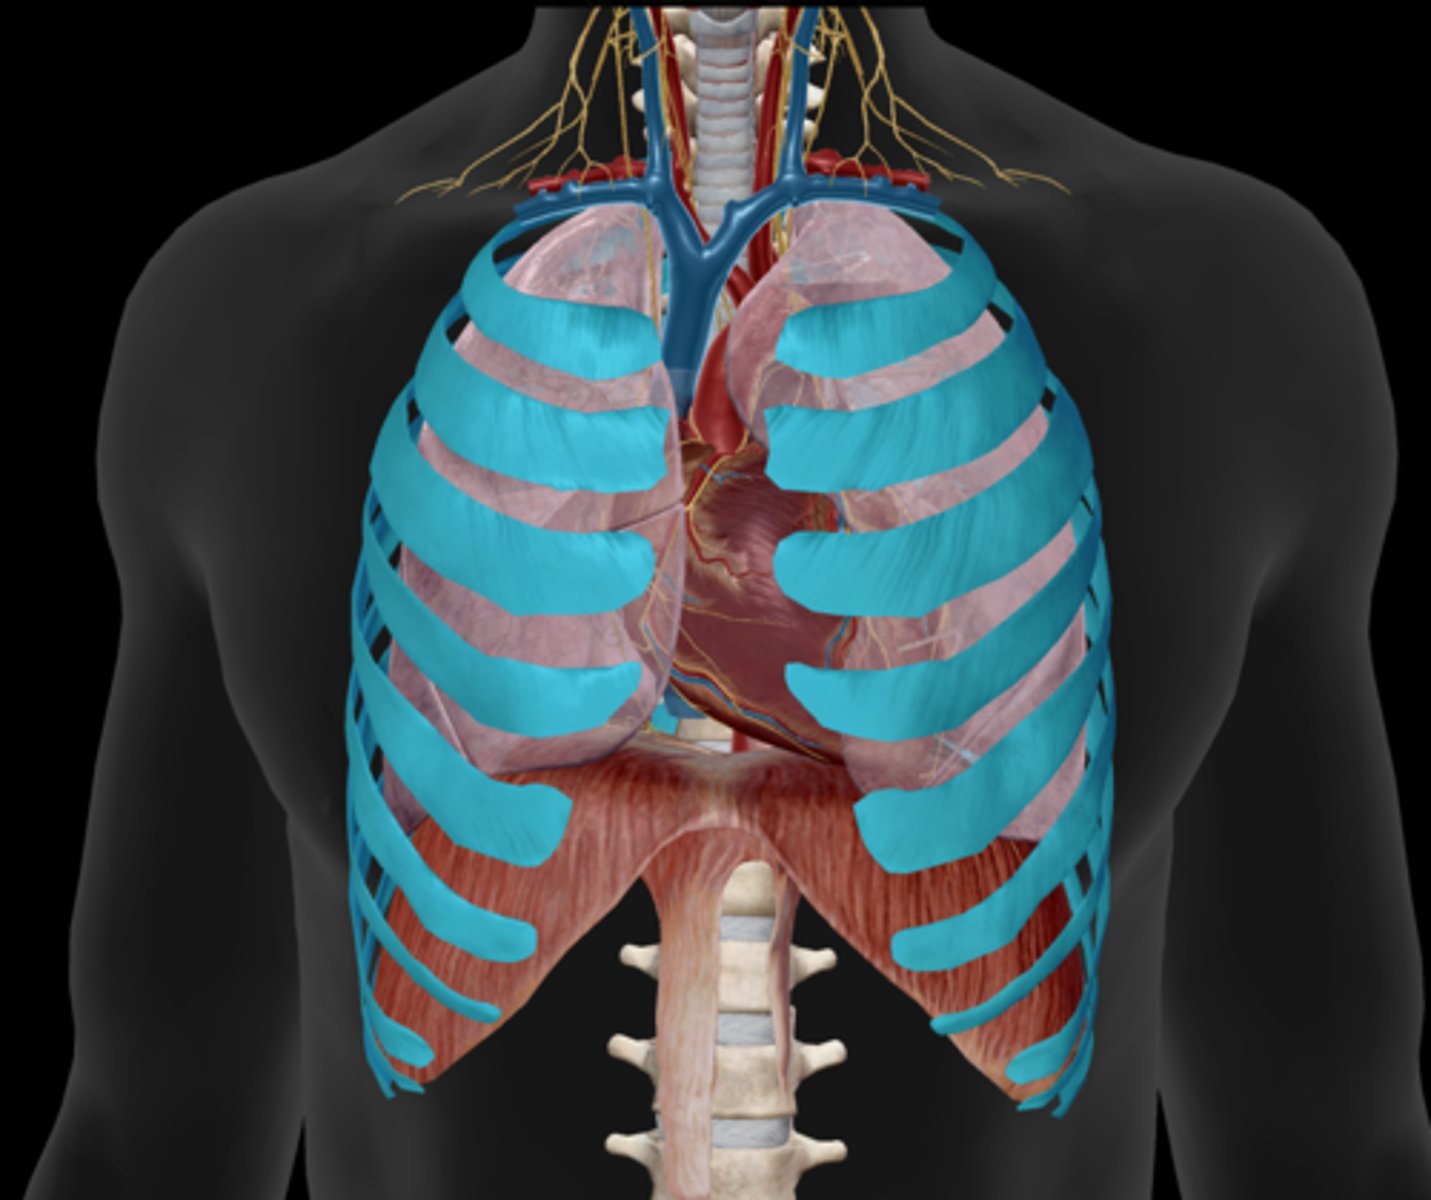

External intercostals

Internal intercostals